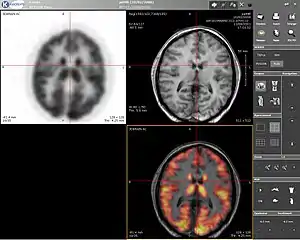

Computer screenshot showing a PET image (upper left), MRI image (upper right) and the combined PET-MRI image where PET data is overlaid over the MRI data (lower right) | |